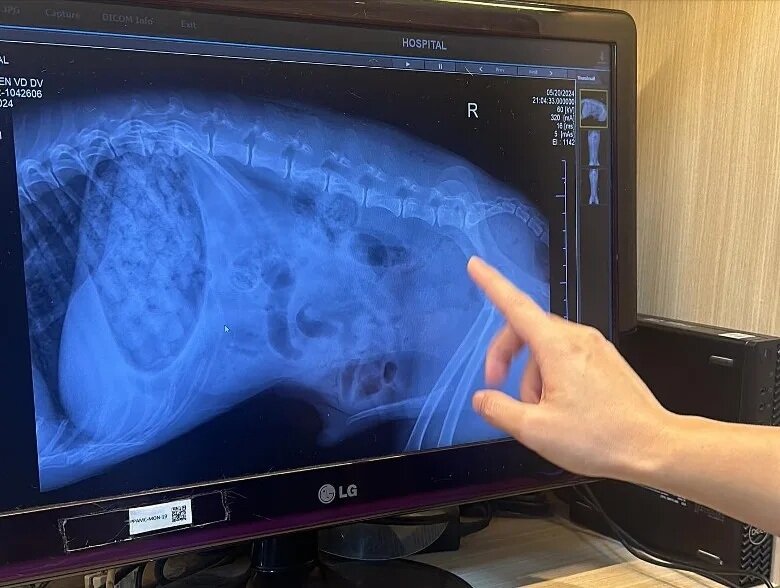

Monnie在社交網上載愛犬在獸醫院留院的相片,見身形嬌小的Whiskey躺在床上,身上插滿了喉管,令聞者心酸。她無奈謂:「我從來沒想過會這樣的一天,我可愛的Whiskey 從來不理會其他狗仔,只愛黐人玩。」又指愛犬被咬傷後,大、小腸受重創致大量出血,由於有生命危險需轉介到醫療設備更完美的市區獸醫院接受緊急手術,她憂心謂:「醫生說牠情況非常差,身上出現的6,7個情況,任何一個都足以令牠致命,如果晚幾小時做手術也沒可能生存……,Whiskey很堅强,現在ICU的牠須繼續觀察,未來這三天是關鍵,希望大家祝福。」